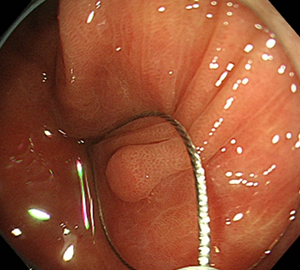

親子方式経口胆道鏡(胆管・膵管)

POCS: peroral cholangioscopy

POPS: peroral pancreatoscopy

当院では、細い内視鏡を主膵管や総胆管に挿入し、管内を観察する検査方法(親子方式経口膵管鏡・胆道鏡検査)を導入しています。直接胆管や膵管を観察することが可能となり、より正確な腫瘍の質的診断(良性か悪性か)や範囲診断に繋げることに加え、結石を視認しながら破石することも可能となりました。